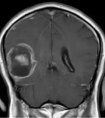

腹部CT扫描是主要诊断方法,可以准确地探查肿瘤的位置和范围,以及肾脏受损程度两岁的男婴小良(化名)活泼好动,最近几周来,他却变得“文静...